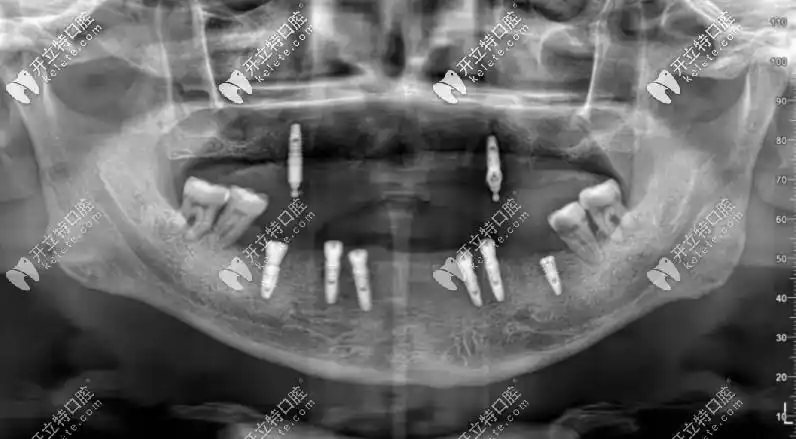

65岁老人全口种了8颗德国camlog种植牙后排骨都敢吃了